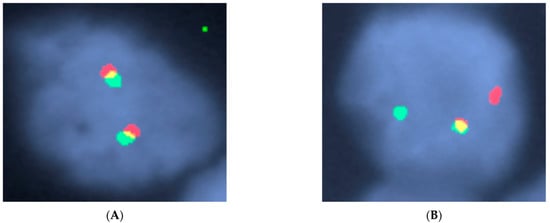

- Tzankov, A.; Xu-Monette, Z.Y.; Gerhard, M.; Visco, C.; Dirnhofer, S.; Gisin, N.; Dybkaer, K.; Orazi, A.; Bhagat, G.; Richards, K.L.; et al. Rearrangements of MYC gene facilitate risk stratification in diffuse large B-cell lymphoma patients treated with rituximab-CHOP. Mod. Pathol. 2013, 27, 958–971. [Google Scholar] [CrossRef] [PubMed]